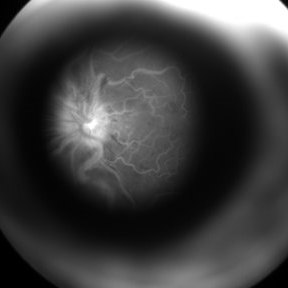

External Image of a Patient with CRVO Undergoing FFA

An external profile photo taken at the end of angiography demonstrates the leaking disc in a patients of CRVO.

Photographer: Miss Ashwini borde

Imaging device: FF 450 Plus IR

Condition/keywords: central retinal vein occlusion (CRVO), external photography